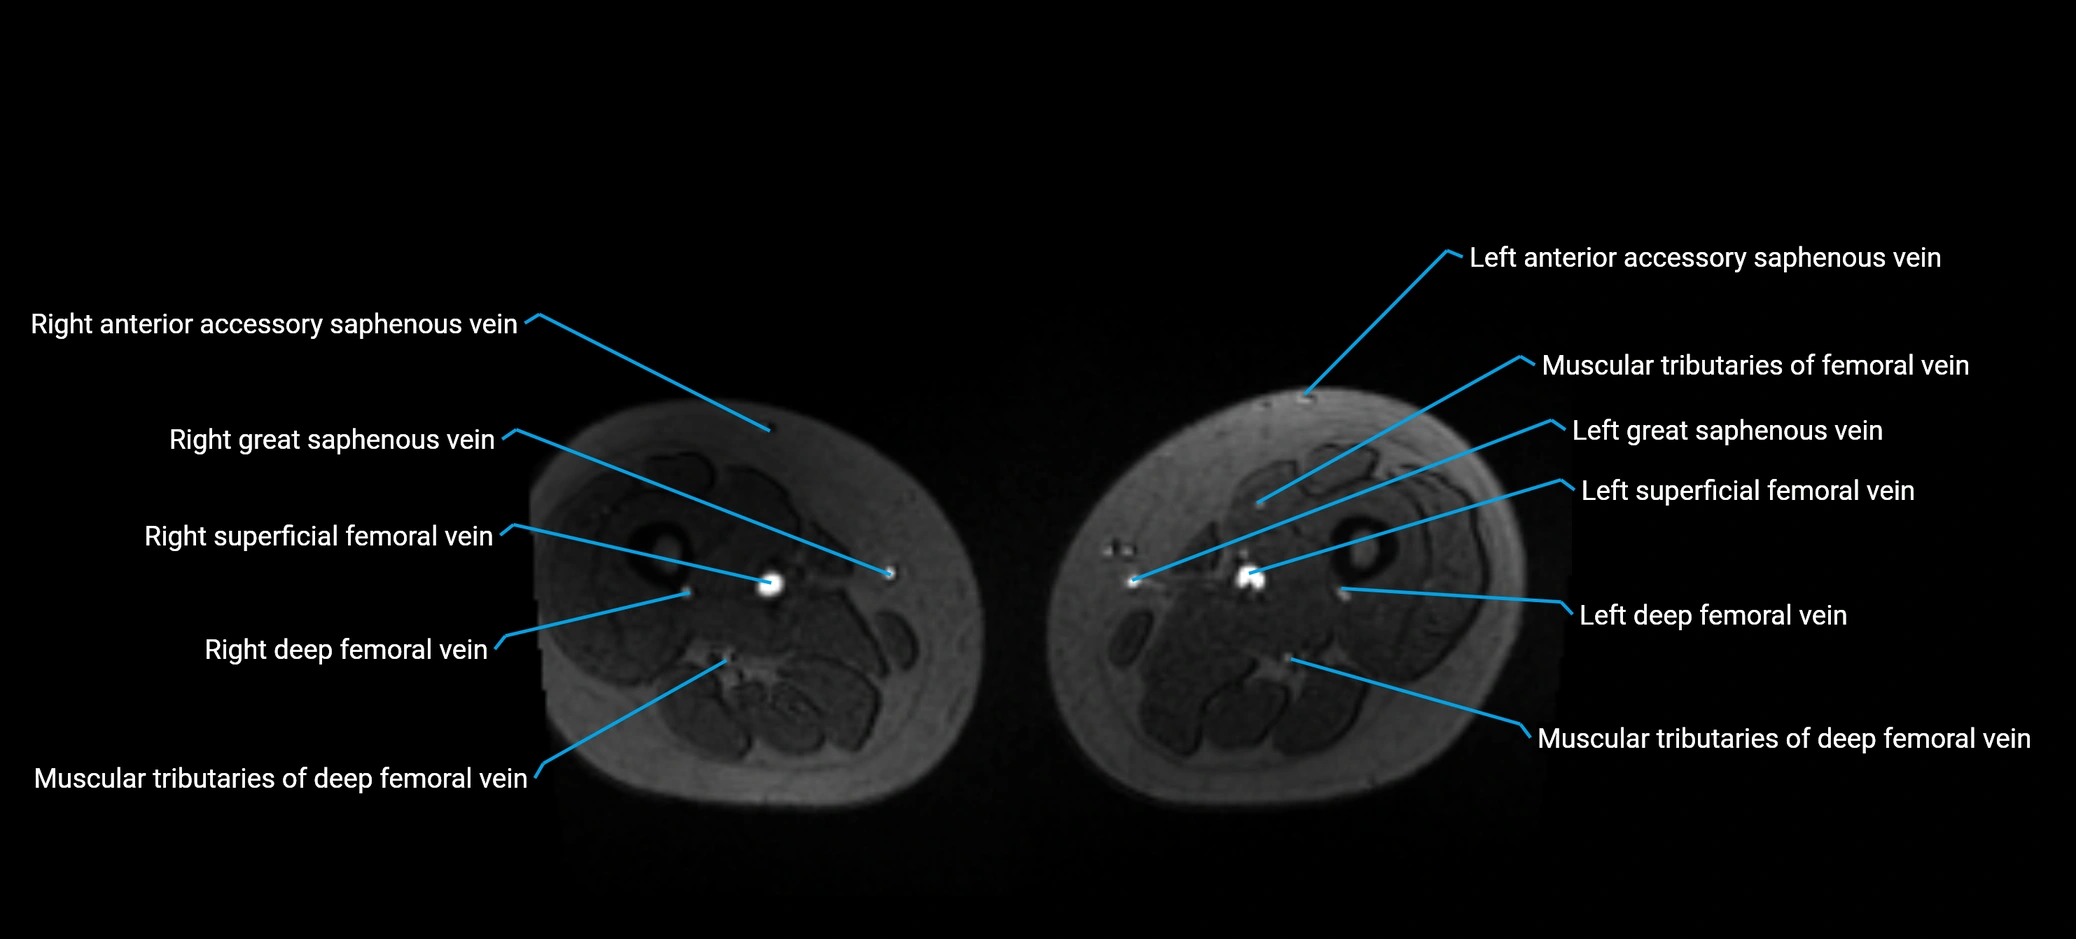

MRI image

image